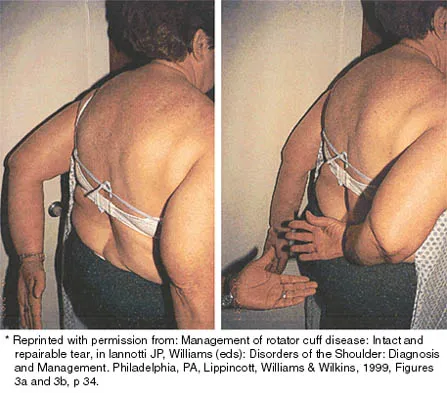

Question 30

A 72-year-old woman who was doing well after undergoing total shoulder arthroplasty for arthritis 4 months ago is suddenly unable to elevate her arm. Examination reveals 70 degrees of external rotation compared with 45 degrees on the uninvolved side, and she is unable to lift her hand off her lower back. Radiographs are shown in Figures 43a through 43c. Treatment should consist of